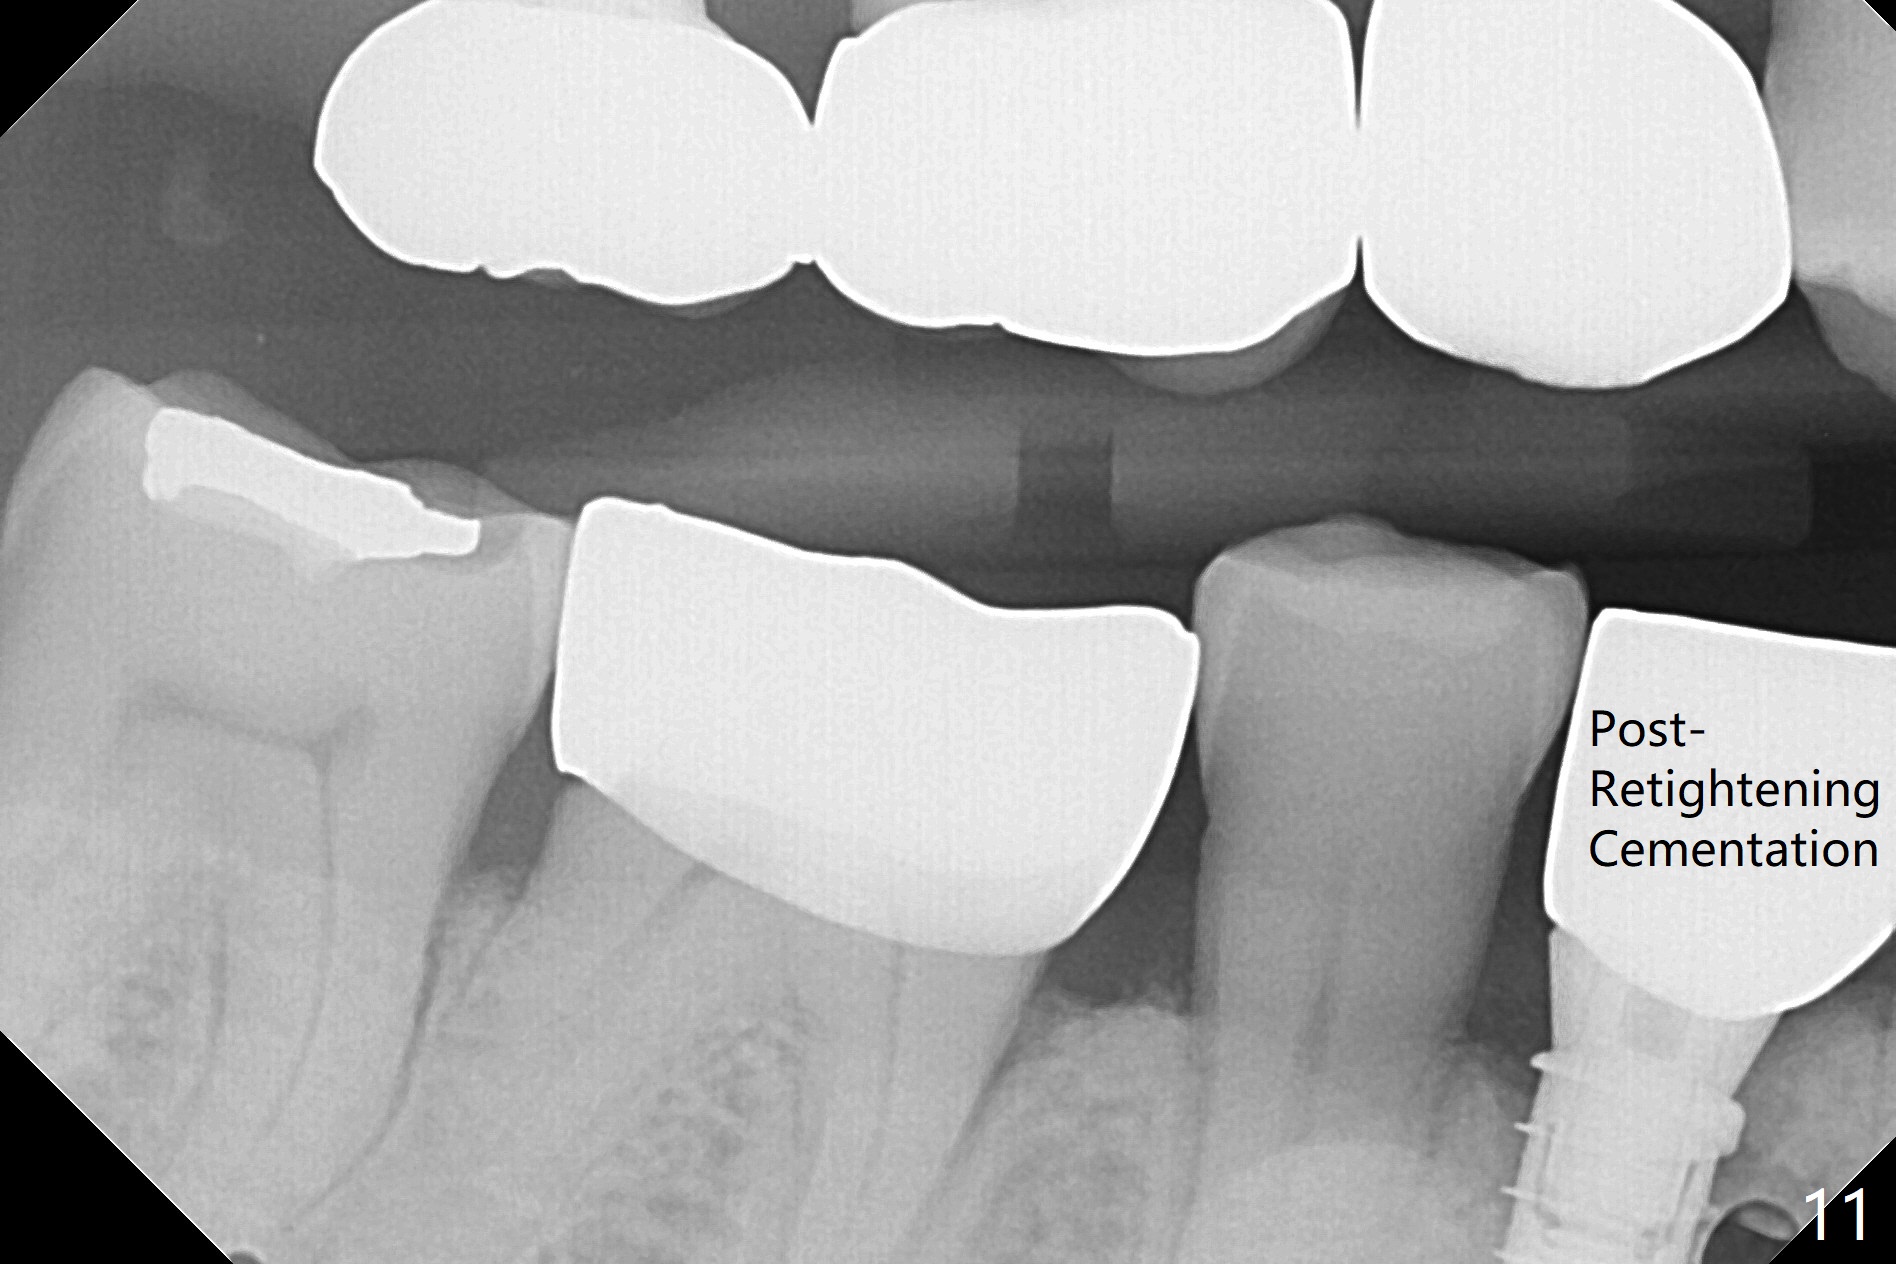

In fact the mesiodistal space of the site of #28 is within normal limit. The buccal plate atrophy is striking (Fig.1) with a fistula (^, associated with underlying residual root tip). When the flaps are raised, the ridge is triangular with the lingual plate (Fig.2 *) higher than the buccal one. Because of the slope, the multiple-drill approach is adopted in stead of single-drill one, because the marking bur is wobbling after 1.6 mm osteotomy at 13 mm (Fig.3). After placement of a 4x11 mm implant, a 4.5x4(2) mm abutment is inserted (Fig.4). The abutment and the implant act as a mesh (framework) so that bone graft and collagen membrane can be laid upon them buccolingually. When the flaps are sutured, there is less tension than that without the abutment. Furthermore, the buccal tissue volume seems to be increased (Fig.5 (<: fistula, which should heal soon), as compared to Fig.1). Tale photos to show effectiveness of the simultaneous GBR and disappearance of the fistula. Three months postop (Fig.6,7 (incomplete abutment seating)), the implant is loaded for intrusion of the opposing supraerupted tooth. The patient returns with chief complaint of food impaction between #27 and 28 three years 7 months post cementation; there is an open contact. Before pick up impression the distal convex surface of #27 is trimmed. The repaired crown has tight proximal contacts before (Fig.9,10) and after (Fig.11) retightening and cementation.